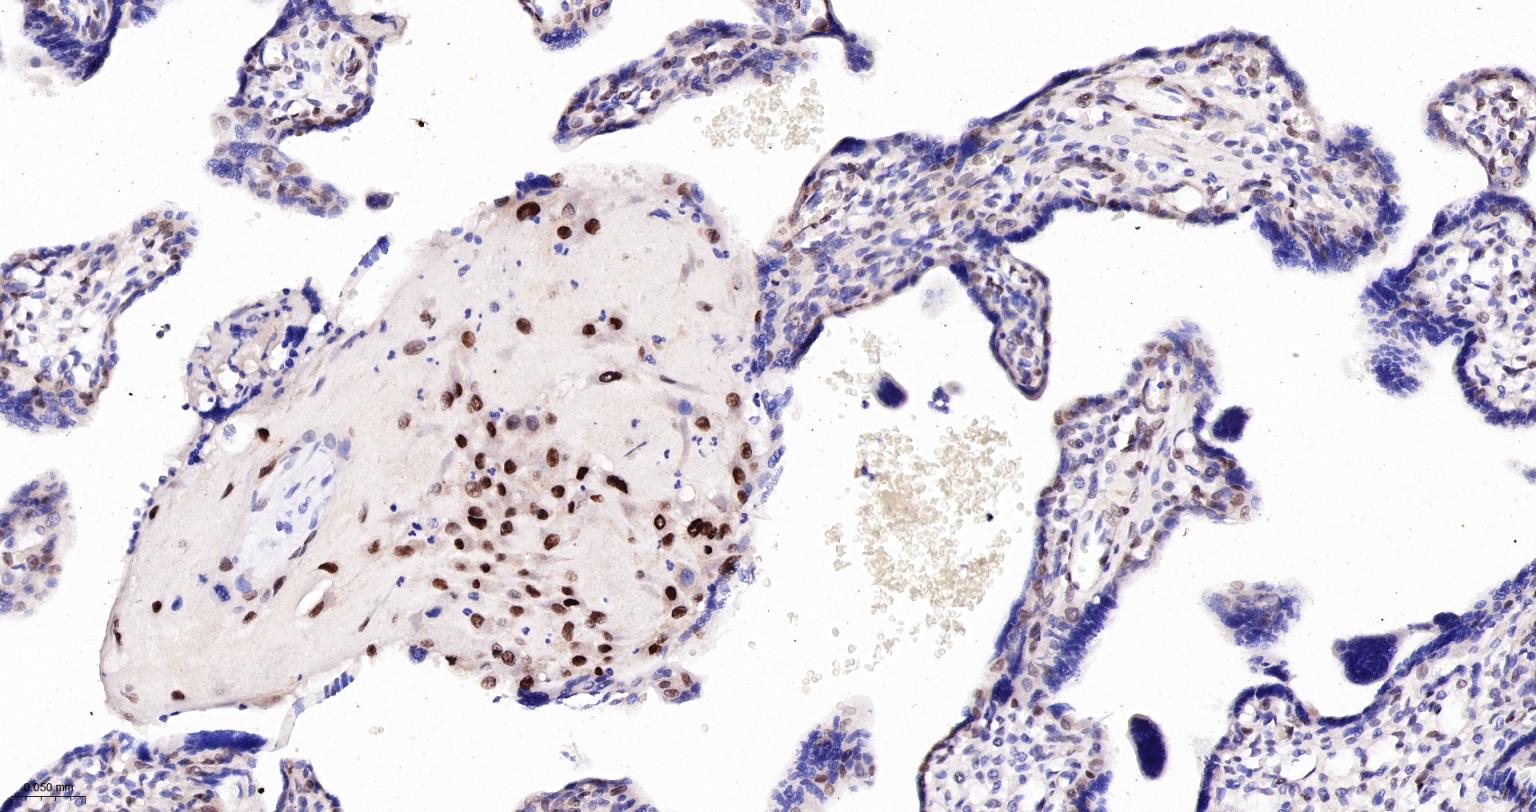

Paraformaldehyde-fixed, paraffin embedded Human Placenta; Antigen retrieval by boiling in sodium citrate buffer (pH6.0) for 15 min; The section was incubated with TEAD1 Monoclonal Antibody, Unconjugated (bsm-63274R) at 1:200 overnight at 4°C, followed by conjugation to the bs-0295G-HRP and DAB (C-0010) staining.